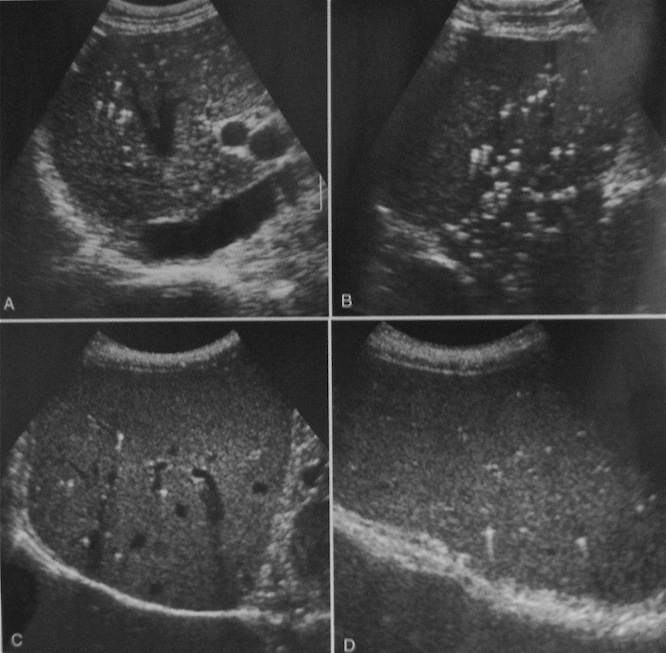

Внутрипротоковые гамартомы

Да, уважаемый ФАМ оказался прав - это внутрипротоковые гамартомы - спасибо Марио.

Что теперь можно смело писать - "множественные гамартомы внутрипеченочных протоков", если встретится такая картина, а она и у меня не раз встречалась?